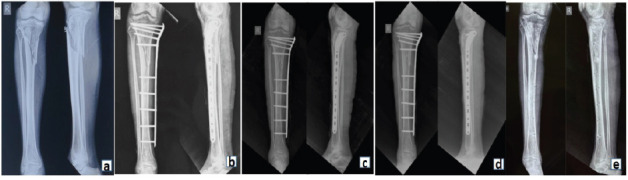

Introduction: Treating metadiaphyseal tibial fractures with compromised soft tissues remains a surgical challenge. While traditional external fixators are widely used, locking compression plates (LCPs) applied externally as fixators offer a promising alternative due to their low-profile design and angular stability.

Objectives: The objective is to evaluate clinical outcomes, union rates, complications, and functional recovery in patients treated with locking plate external fixators (LPEFs) for metadiaphyseal tibia fractures.

Materials and methods: This prospective study of 15 adult patients with open or soft-tissue-compromised metadiaphyseal tibia fractures was conducted over 12 months. All patients were managed using LCP as an external fixator. Radiological union, time to weight-bearing, infection rates, reoperation need, and functional outcomes (knee society score [KSS] and the American Orthopaedic Foot and Ankle Society [AOFAS]) were assessed.

Results: The mean time to union was 12.1 weeks, with a union rate of 90%. One superficial infection (6.6%) and one reoperation (6.6%) were noted. The final follow-up revealed excellent functional outcomes: Mean KSS score of 85 ± 5 and AOFAS of 81 ± 4.

Conclusion: LPEF offers a viable fixation method in managing complex tibial fractures with soft-tissue compromise, allowing early mobilization, fewer complications, and excellent functional outcomes. Larger studies are needed to validate its widespread adoption.